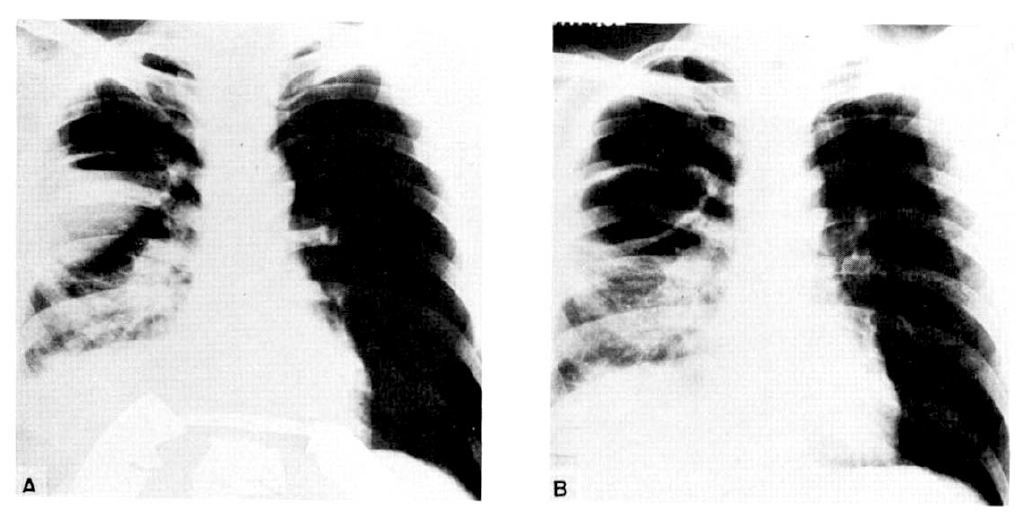

Fig. 1. and 2. are the X-rays of two cases which showed great success.

Fig. 1.

(Patient No. 2): (A) Chest PA shows an abscess with a high air-fluid level; the lesion was located in the superior segment of the right lower lobe, and was intractable to postural drainage and antibiotic therapy. (B) After fiberoptic bronchoscopy and catheter drainage, a dramatic effect is noted in this film taken 4 hours later.